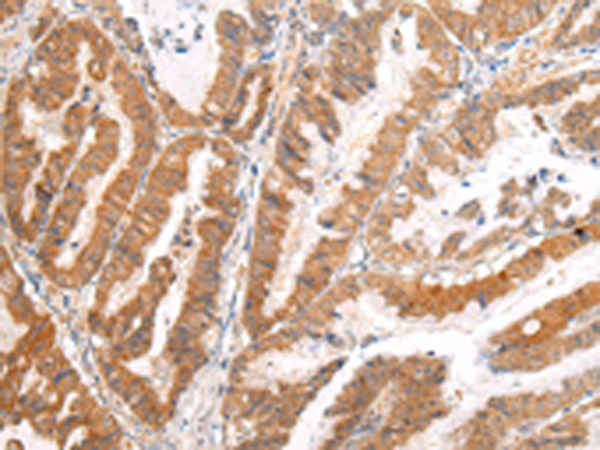

分类: 科研抗体货号: P12486别名: CDX3; CDX-3; CDX2/AS应用: WB,IHC反应种属: Human, Mouse